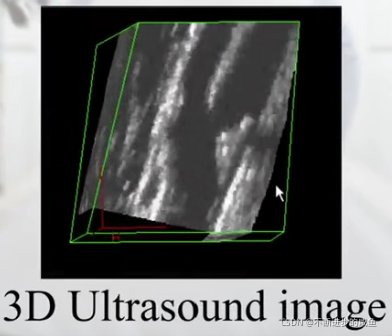

三维图像:一个像素描述成一个体素。

(2)三维图像:被描述成f(i,j,k)

(8)超声图像:

(4)超声图像: 超声图像很难看懂,因为图像视野狭窄,图像精度也不好,但是绿色对人体无害。

(6)三维超声